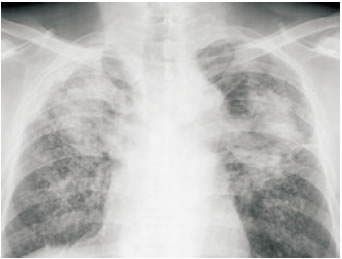

粉塵沉積的肺部X光造影(圖片來自網(wǎng)絡(luò))

具體來說,當粉塵顆粒進入肺泡內(nèi)部或者間隔時,雖然大部分可以通過呼吸作用被排出體外,仍有小部分吸附、沉積下來,最終對肺部造成以下幾種可能的潛在惡劣影響:

1. 肺泡細胞遭到破壞,取而代之的是失去了正常機能的纖維組織,稱為肺部纖維化。

2. 肺泡彈性喪失。

3. 支氣管炎癥,哮喘。

上述提到的肺部纖維化是不可逆轉(zhuǎn)的組織病變,一旦發(fā)生,肺功能就無法恢復到原先的水平。目前的醫(yī)學科技無法對纖維化后的組織實現(xiàn)轉(zhuǎn)化,發(fā)病后只能緩解癥狀,無法徹底根治,這也是塵肺病被稱為是某種意義上“絕癥”的原因。